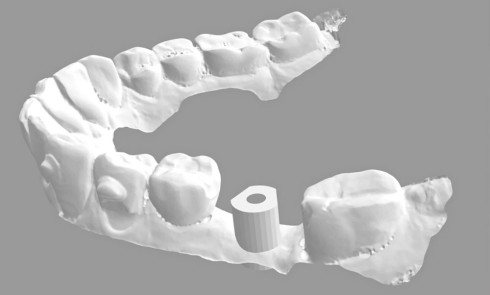

Les couloirs prothétiques sont généralement décalés par les phénomènes de résorption : centrifuge à la mandibule dans les secteurs postérieurs et centripète dans la zone antérieure ainsi que sur l’ensemble de l’arcade maxillaire.